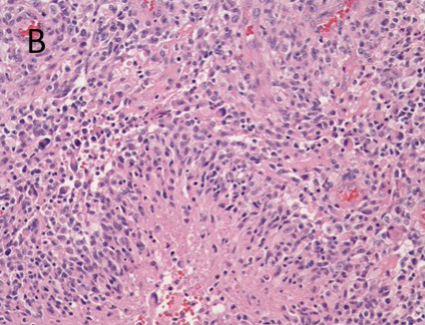

A. T1-post contrast MRI showing a right parietal, rim-enhancing lesion. B. H&E of the tumor showing endothelial proliferation with palisading necrosis C. ALK positively in ~5% of tumor cells.

Glioblastoma is the most frequent malignant brain tumor in adults, accounting for approximately 40-50% of all primary malignant tumors in the brain. The tumor most often centered in the subcortical white matter and deeper grey matter of the cerebral hemispheres. On imaging study, glioblastomas are irregularly shaped and have a ring-shaped zone of contrast enhancement around central area of necrosis. Typical pathologic features include prominent microvascular proliferation and palisading necrosis.